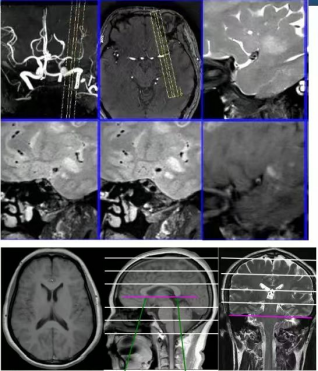

3.0T高端磁共振:这台先进的磁共振设备不仅具有超高的分辨率,还能进行不打药灌注(ASL),颅内血管壁高清成像,突破了传统影像学的局限。